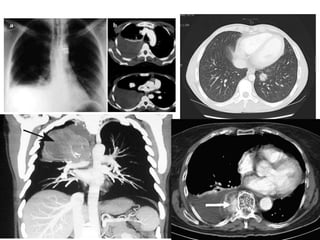

» RADIOGRAFÍA SISTEMÁTICA DE TORAX:

→ Incluye por regla general una proyección posteroanterior y otra

lateral.

→Rx en sentido anteroposterior en caso de px críticos

→ estudio diagnostico de las enfermedades del parénquima pulmonar,

la pleura y en menor medida las vías respiratorias y el mediastino.

→ Proyección en decúbito latera ayuda a la detección de liquido libre en

la pleura.

→ Proyecciones lordoticas permiten examinar mejor los vértices

pulmonares.

• Permite detectar

• Tumor pulmonar

• Neumonía

• Tuberculosis

» Tomografía computarizada:

→ofrece diversas ventajas sobre la rx de tórax:

1. Permite distinguir las densidades que se

superponen en una rx simple.

2. Define mejor las densidades de los tejidos y

separa pequeñas diferencias de densidad entre

estructuras vecinas

3. Permite evaluar el tamaño exacto de las lesiones

4. Identificación de zonas con densidad grasa o

calcificada en los nódulos pulmonares .

Permite evaluar el tamaño exacto de las lesiones en

los pulmones.

1. coágulos de sangre

2. hemorragias internas